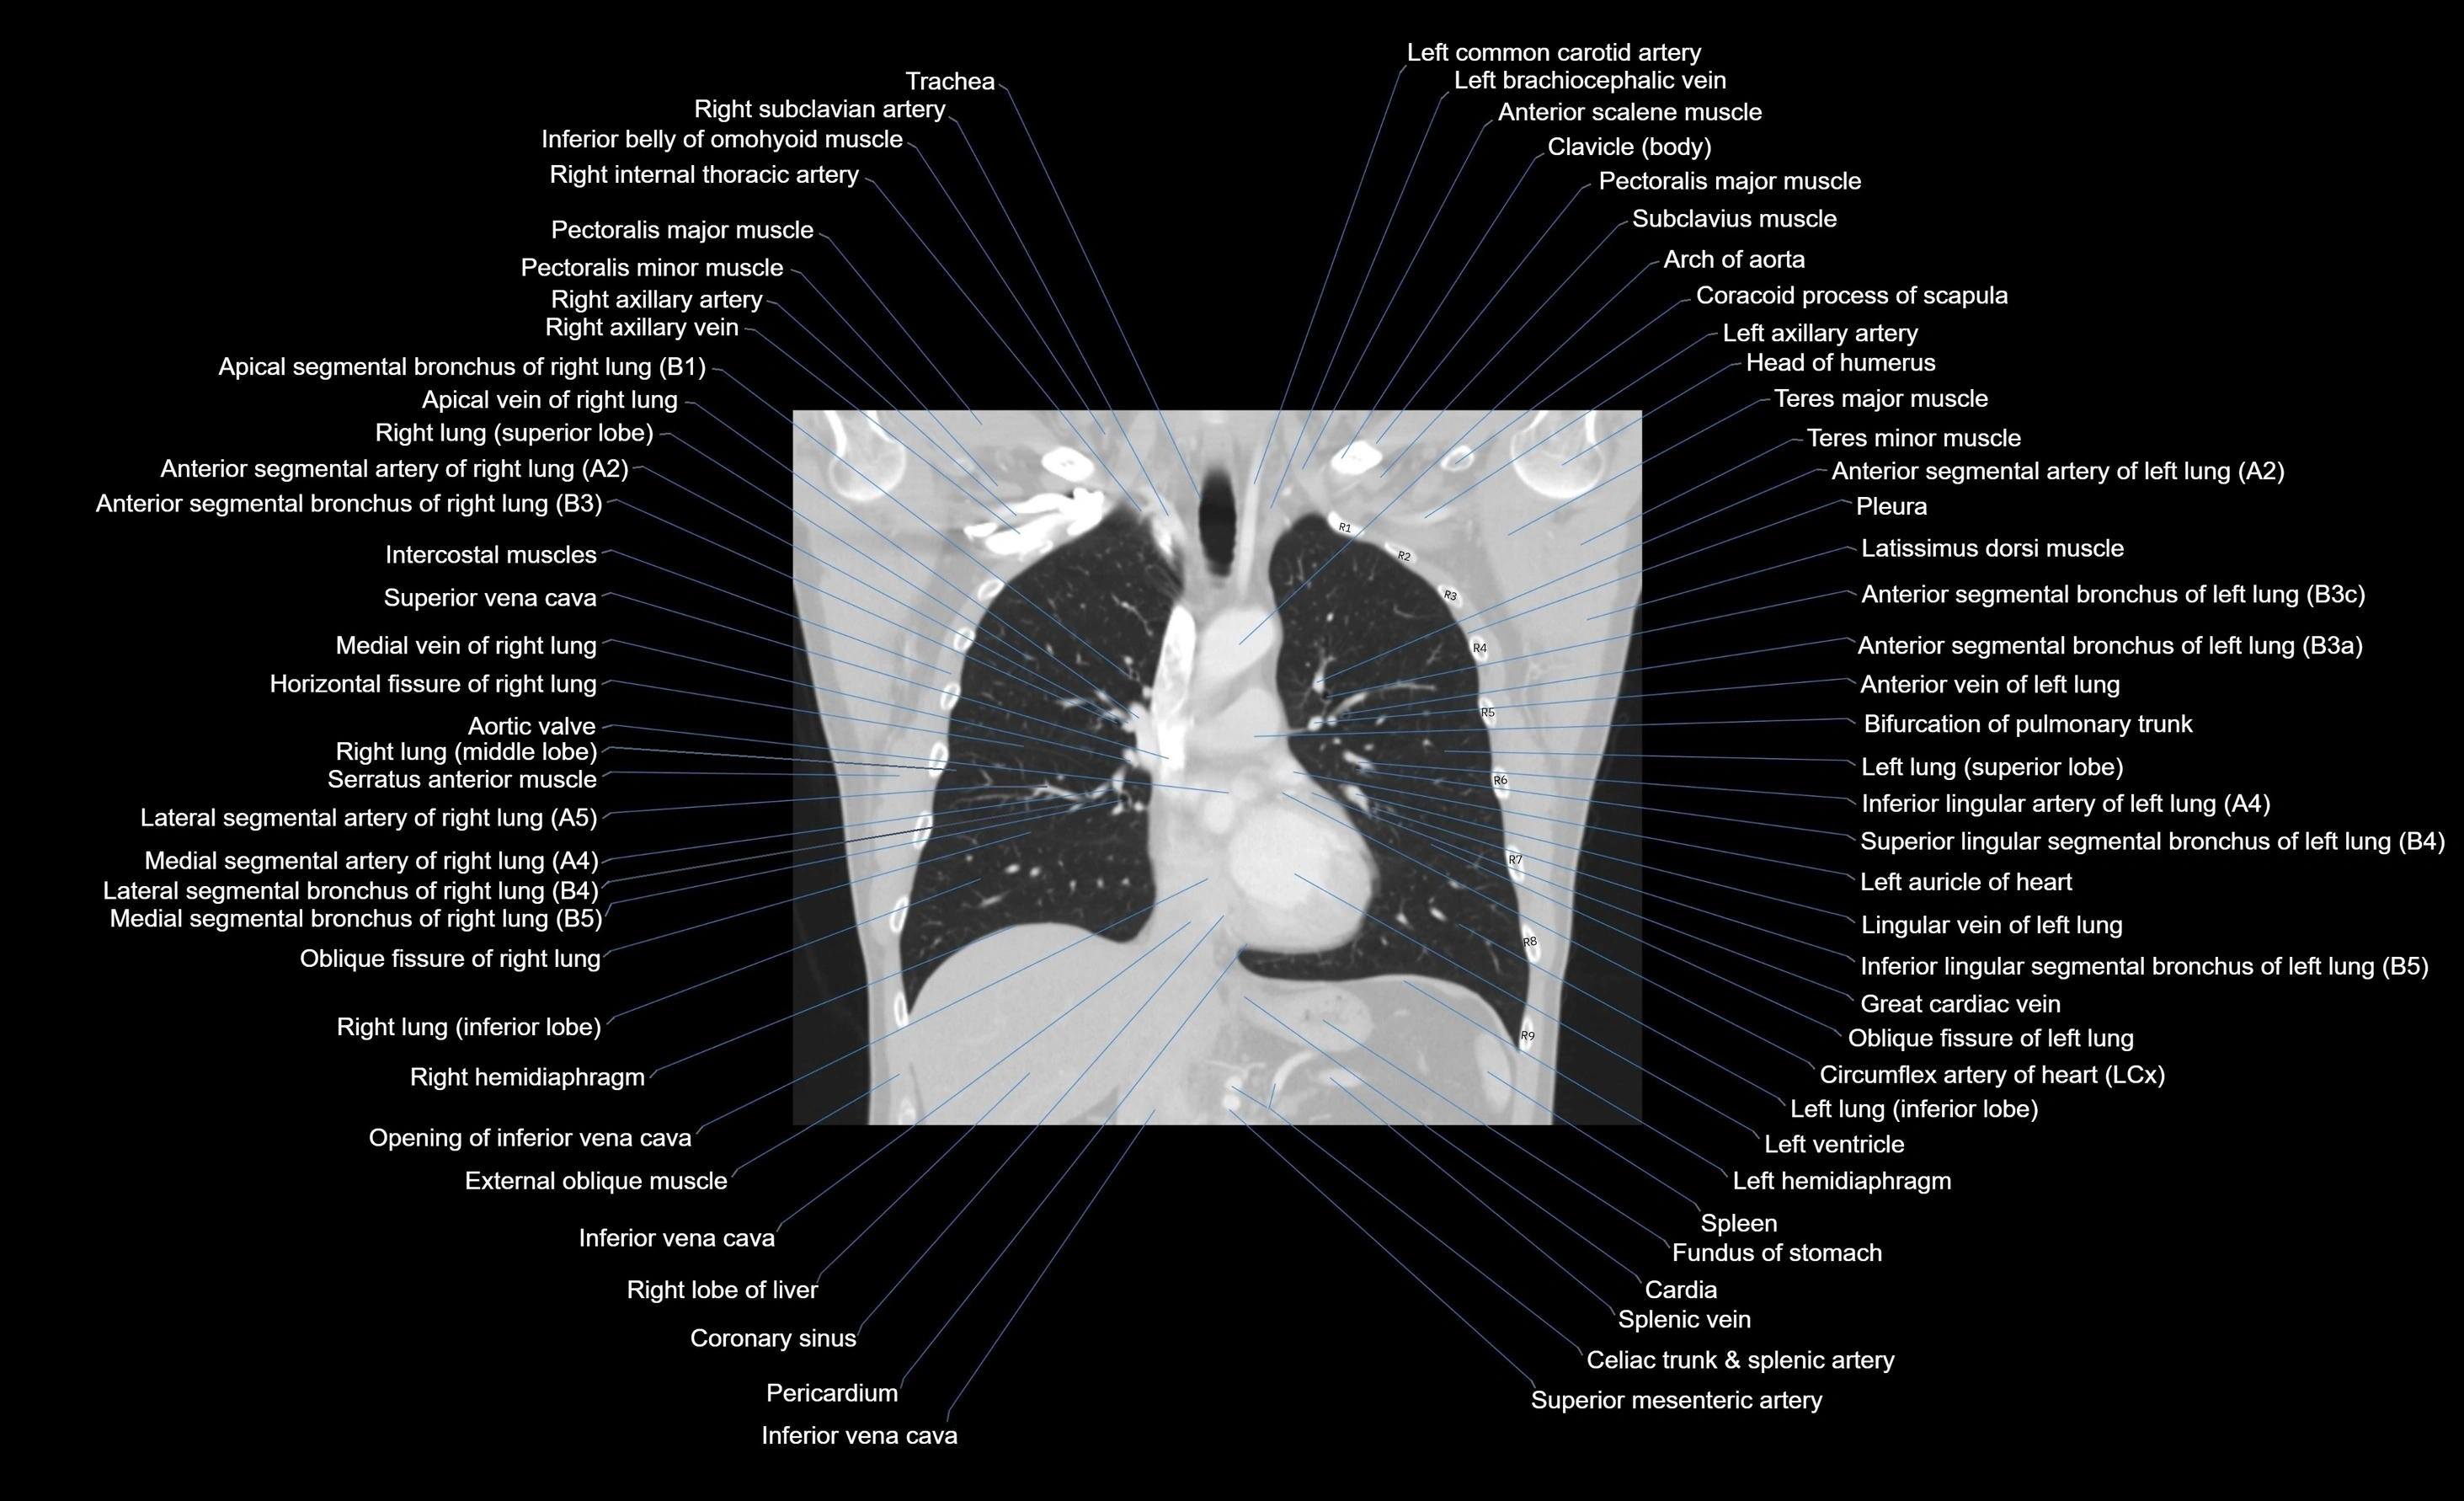

- Arch of aorta

- Ascending aorta

- Brachiocephalic trunk

- Clavicle

- Coracoid process of scapula

- Coronary sinus

- Great cardiac vein

- Horizontal fissure of right lung

- Inferior vena cava

- Left atrium

- Left brachiocephalic vein

- Left common carotid artery

- Left hemidiaphragm

- Left lung (inferior lobe)

- Left pulmonary artery

- Left subclavian artery

- Left ventricle

- Middle lobe of right lung

- Oblique fissure of left lung

- Oblique fissure of right lung

- Pectoralis major muscle

- Pectoralis minor muscle

- Right hemidiaphragm

- Right lobe of liver

- Right ventricle

- Serratus anterior muscle

- Spleen

- Superior mesenteric artery (SMA)

- Superior vena cava

- Teres major muscle

- Teres minor muscle